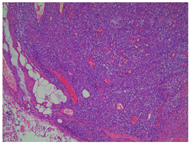

例1患者肿瘤细胞排列呈片状、索条样及网状,或形成交通状的血窦网,位于肠壁全层。瘤细胞呈上皮样,大小比较一致;核呈圆形、卵圆形或梭形,细胞核大、淡染;部分细胞核可见小核仁,异型性明显,核分裂像易见(图2,图3图4);间质伴灶片状出血。与2年前左大腿外侧及左侧腹股沟EA肿瘤组织学相似(图5)。

例2患者上皮样肿瘤细胞呈实性片状排列,位于黏膜下、肌层及浆膜层。瘤细胞呈圆形及卵圆形,核大淡然,异型性更明显;可见大红核仁,局部可见血窦及血管网结构;间质可见慢性炎细胞浸润(图6,图7图8)。与1年前左肺上叶EA肿瘤组织学结构类似(图9)。